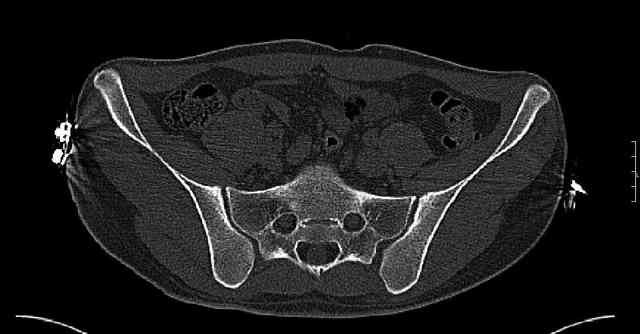

Some more images. Does it help to guess which part of the acetabulum is displaced?

Normal appearing SI joints and a healed posterior column limb... my bet's on caudal segment displacement.

While not claiming to have the best 3D brain around, it appears to me from the limited images available, that the caudal segment is stable from the symphysis to the SI joint on the fracture side. I would love to see the rest of the transverse CT images to see where the fracture line actually exits posteriorly on both the inner and outer tables of the ilium. In my hands,

assuming that the femoral head has followed the cephalad (dome) fragment, I would use an ilioinguinal approach and take down the fracture line from anterior to posterior, distracting with a lamina spreader, if necessary, to clean out and inspect the joint. I would then reduce the cephalad fragment to the caudal fragment using jungbluth or farabeuf clamp and screws and then apply a plate and screws. If the fracture exits posteriorly would you then favor an additional posterior approach to clean out and reduce from that side?

My concept is that what I am after is restoring the anterior portion of the acetabular ring to the superior dome portion to re-establish the containment of the femoral head in an intact "horseshoe". Is this accurate?